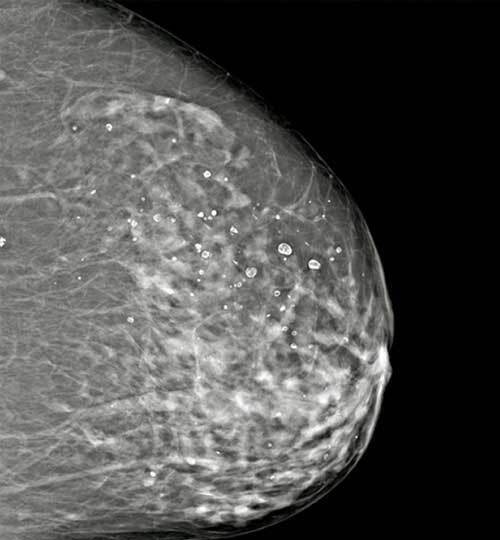

Le dépistage est fait par mammographie numérique. Une nouvelle technique, la tomosynthèse, qui consiste non plus à acquérir deux images fixes du sein, mais un volume d’images, par un déplacement du tube de rayons X sur une angulation définie, permet de s’affranchir des effets masquants du tissu mammaire sur d’éventuelles lésions, et d’augmenter ainsi le taux de détection des cancers, principalement invasifs, en particulier dans les seins denses. Non encore utilisé en dépistage organisé, elle est en cours d’évaluation par la HAS.